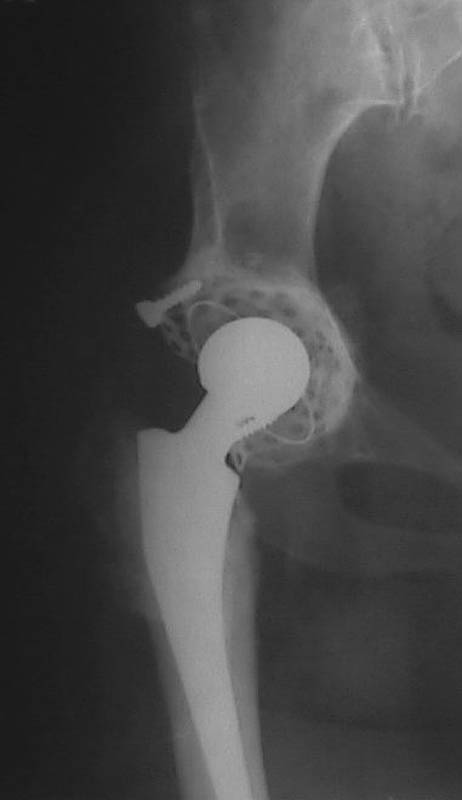

Мужчина, 38 лет. Двусторонний диспластический коксартрз, кифосколиоз.Правый сустав прооперирован 12.12.00, левый - в апреле 2003 г. Справа вывихнулась <чашка>.

Предполагается заменить <чашку>, наростив крышу <тутопластом>? Возможно ли использовать бесцементную <чашку>? Мнения? Заранее благодарю! С уважением,А.В.Владзимирский